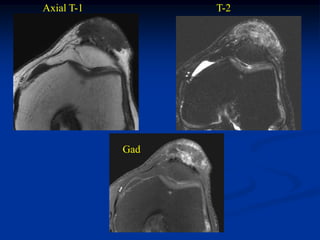

Case #6                                  Tophaceous gout

synovial sarcoma pseudotumor

51 year male with tender prepatellar lump for three years

Axial T-1         T-2

Gad

Sag T-1   T-2